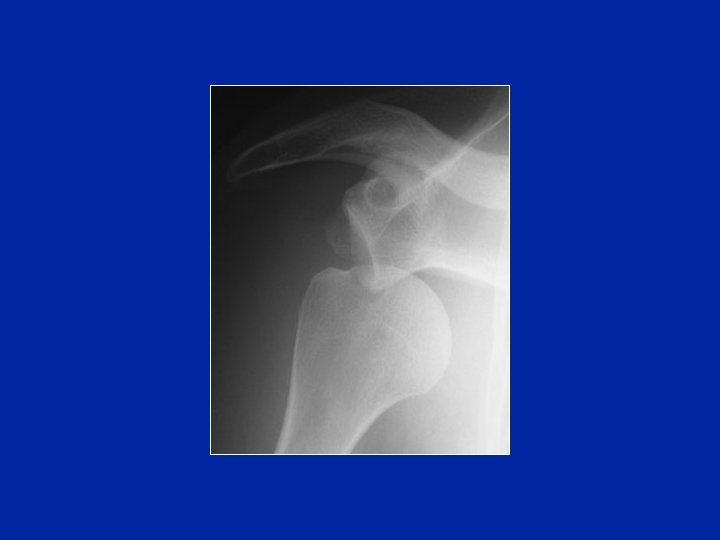

Fractures-luxations

Énucléation